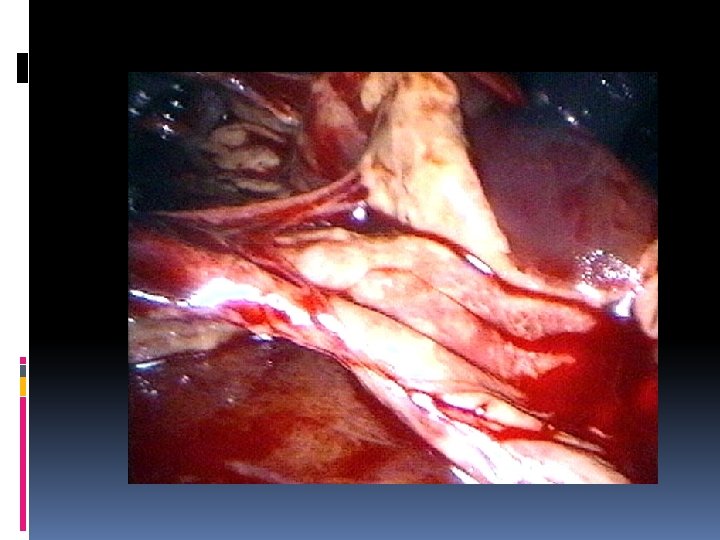

EMPIEMA PLEURICO VATS Essenziale per un trattamento adeguato e per prevenire la cronicizzazione è un drenaggio adeguato del cavo pleurico che permetta al polmone di riespandersi (obliterando il cavo pleurico) e che oggi viene attuato con chirurgia miniinvasiva. La VATS (Video Assisted Thoracic Surgery) permette di • evacuare completamente il contenuto dell’empiema • operare un’adeguata toilette • rottura delle eventuali sacche formatesi ed asportazione dello strato di fibrina dalla superficie del polmone • inserire visivamente il tubo di drenaggio nella posizione più appropriata

EMPIEMA PLEURICO VATS Tale procedura può essere, inoltre, messa in atto in anestesia locale potenziata (con sedazione più o meno marcata), (pazienti ad alto rischio). E’ importante che il drenaggio sia chiuso (con valvola ad acqua tipo Bulau), di diametro sufficiente e declive.